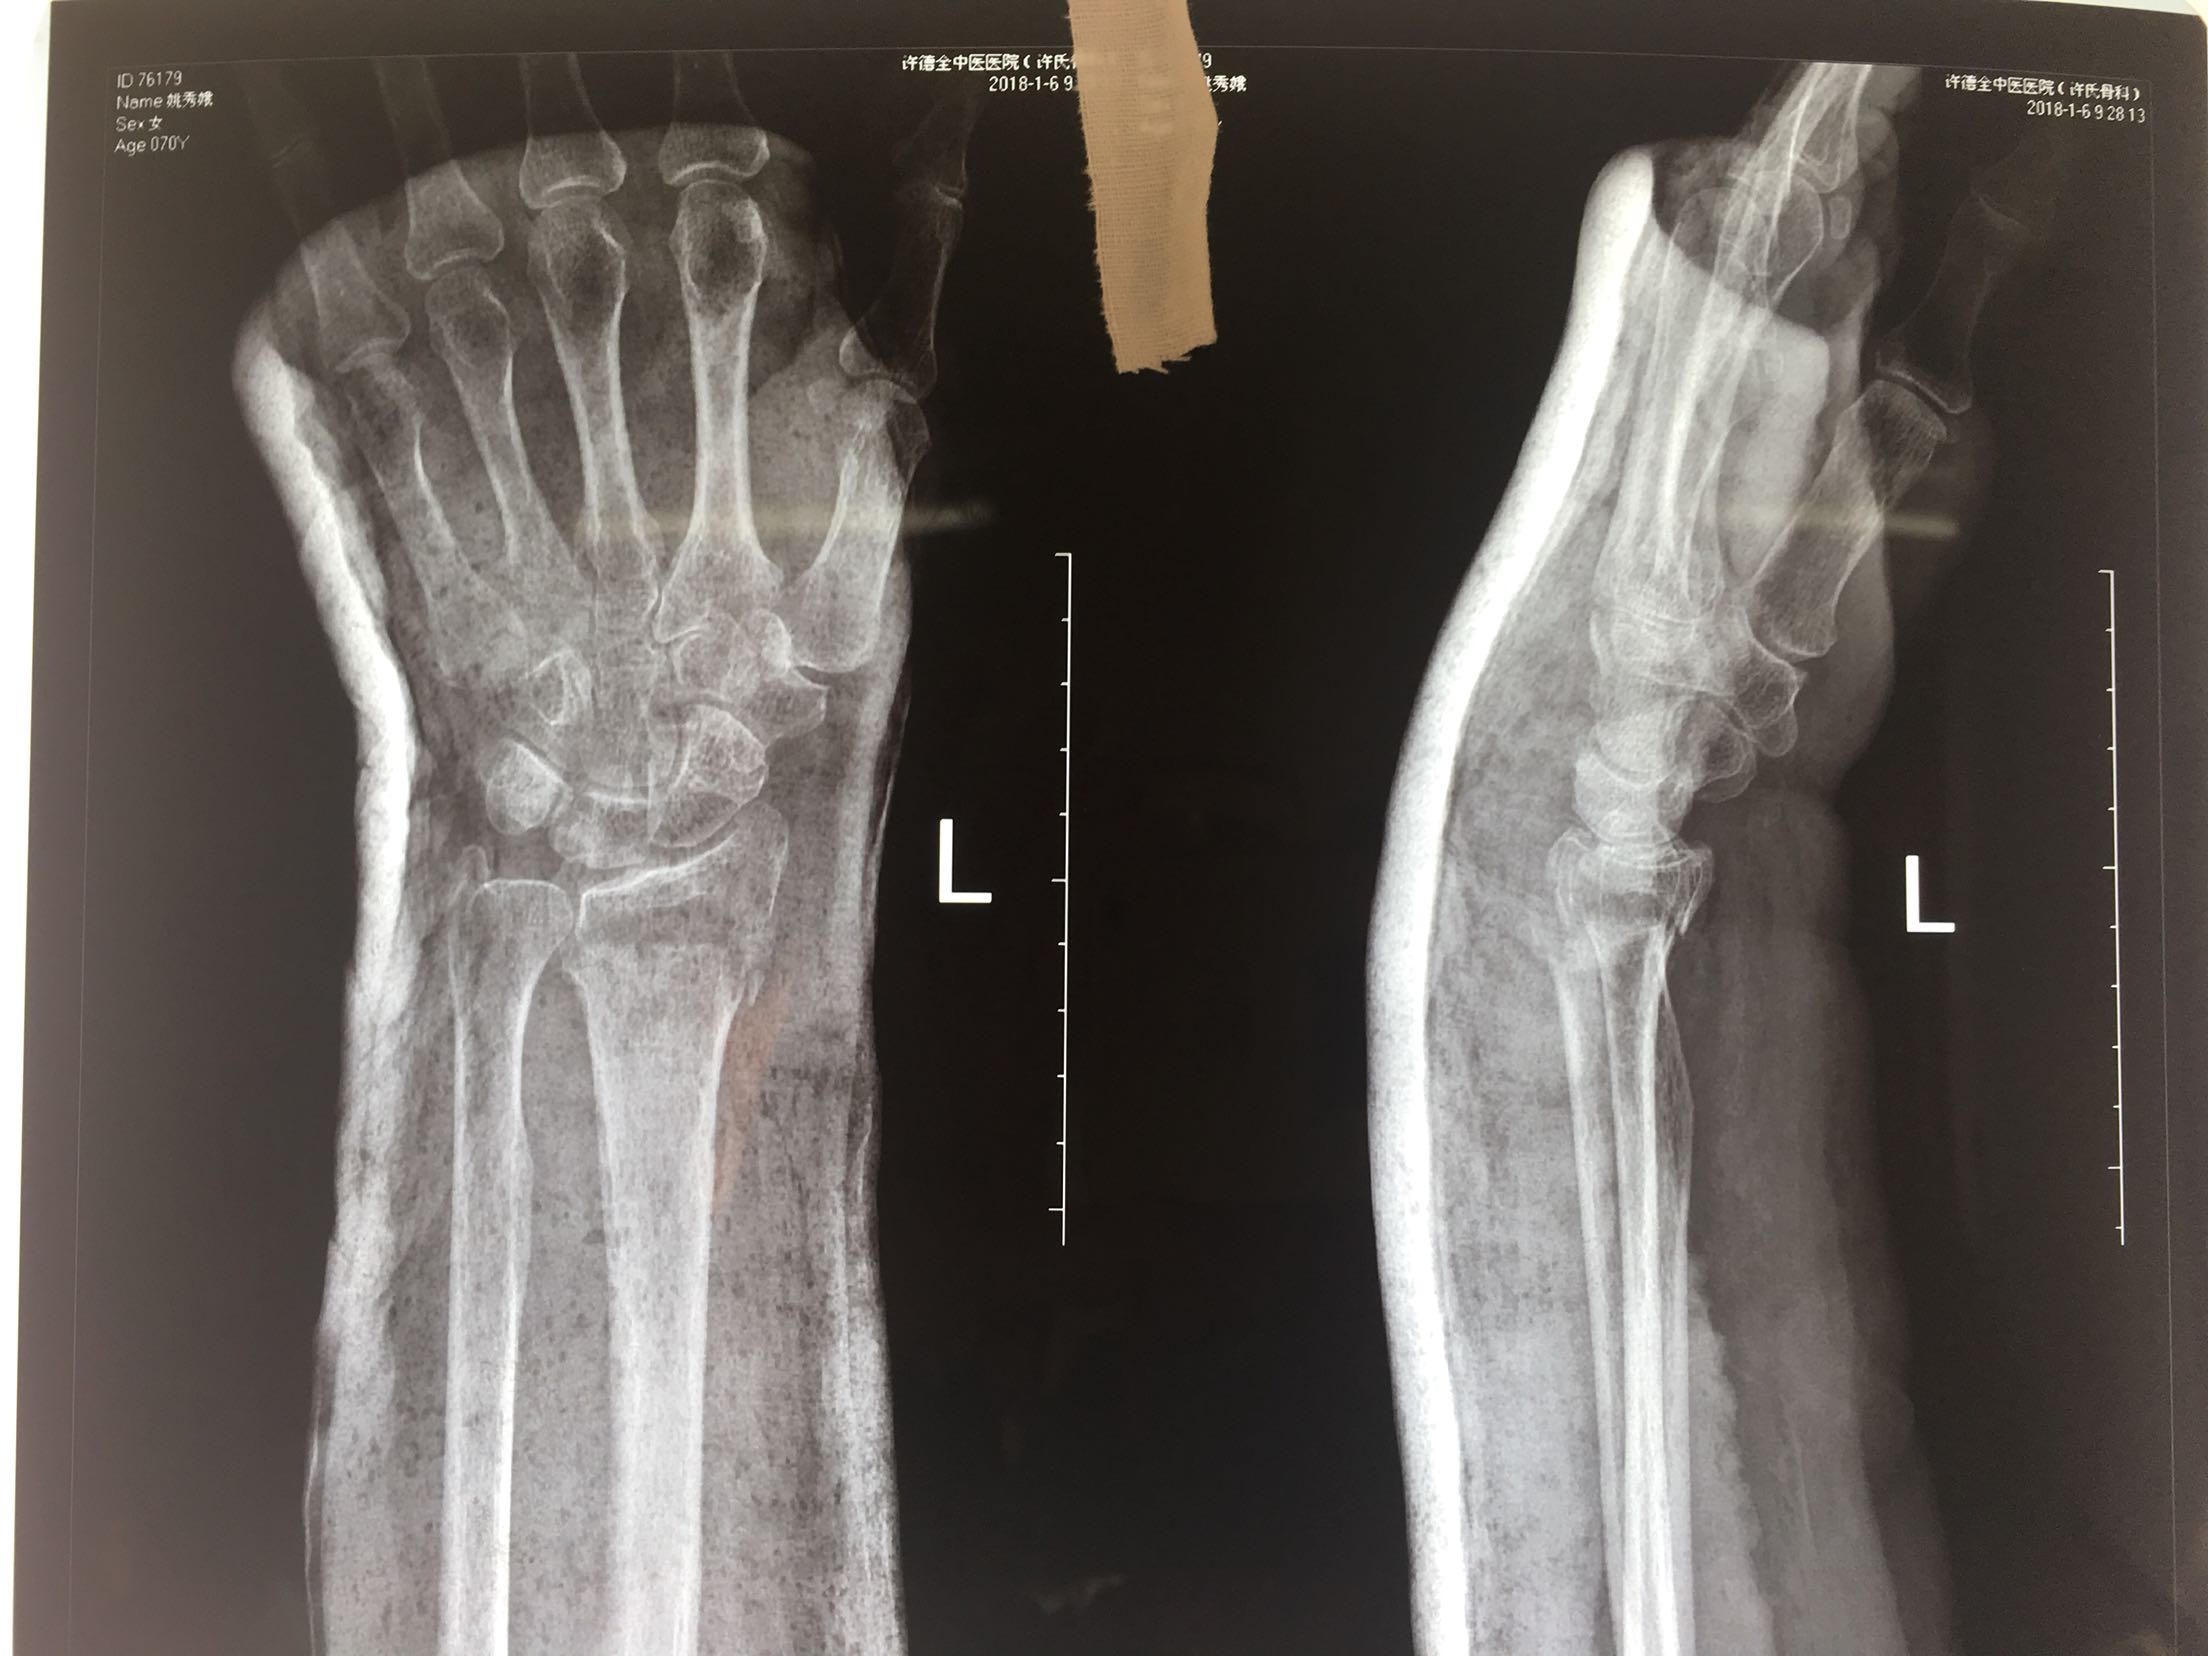

一例保守治疗失败的colles骨折

患者,女性,70岁,摔伤后左腕关节肿痛畸形3天。

在臂丛麻醉下行切复内固定术,术后抗炎,消肿对症处理。